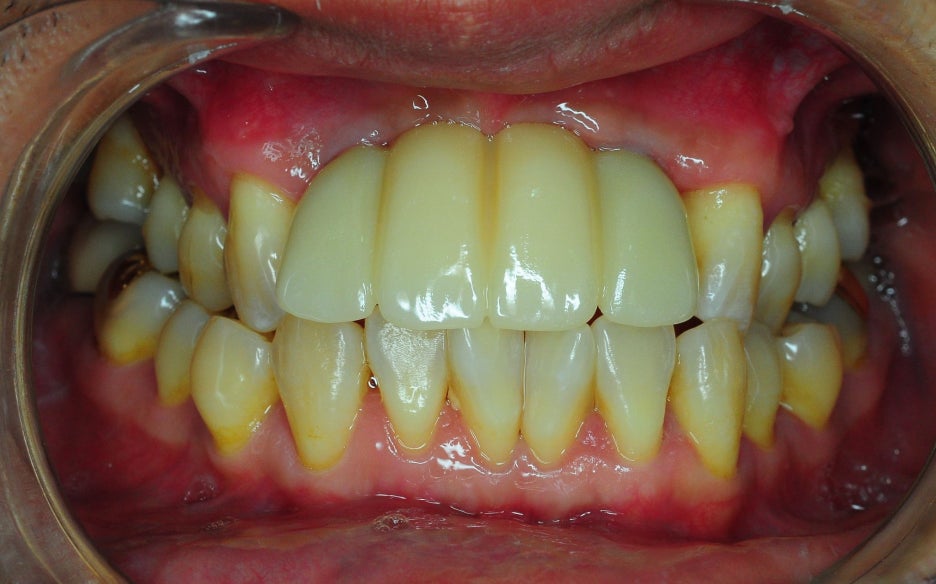

< Some implant surgery cases >

Problem tooth location: mandibular anterior region